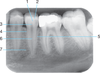

Amalgam

Dental base

2.

Radiopaque amalgam restorations

PDL space

2.

Mylohyoid ridge

Full metal crowns form bridge abutments

Identify #1.

Border of maxillary sinus

PDL Space

6.

Post and core